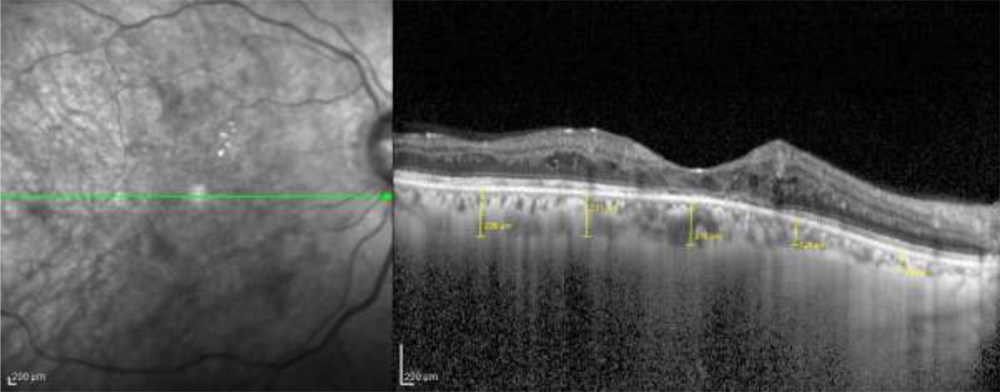

Enhanced depth imaging optical coherence tomography (EDI-OCT (Spectralis HRA + OCT, Heidelberg Engineering) was performed for all patients. CT was measured manually with the help of built-in callipers in OCT software. Measurements weremadefrom the outer portion of hyperreflective line corresponding to the retinal pigment epithelium to the inner portion of hyperreflective zone corresponding to choroidoscleral junction by a single masked observer. They were obtained in the subfoveal region (Subfovealchoroidal thickness; SFCT) and at a distance of 1500µm and 3000µm from the locus of measurement of SFCT in nasal and temporal quadrants (N1500, N3000, T1500, T3000) (Figure 1). Automated central macular thickness (CMT) was calculated using the 25-line raster scan protocol. After 12 hours of overnight fasting, blood samples were collected for estimation of blood urea, serum creatinine and serum HbA1C levels.

Figure 1: Horizontal enhanced depth imaging optical coherence tomography (EDI-OCT) scan of the same 63/M diabetic patient with presence of retinopathy changes. The choroidal thickness was measured from the outer portion of hyper-reflective line corresponding to the retinal pigment epithelium to the inner portion of hyper-reflective zone corresponding to choroido-scleral junction in the sub-foveal region (SFCT) and also at a distance of 1500µm and 3000µm from the locus of measurement of SFCT in nasal and temporal quadrants (N1500, N3000, T1500, T3000).